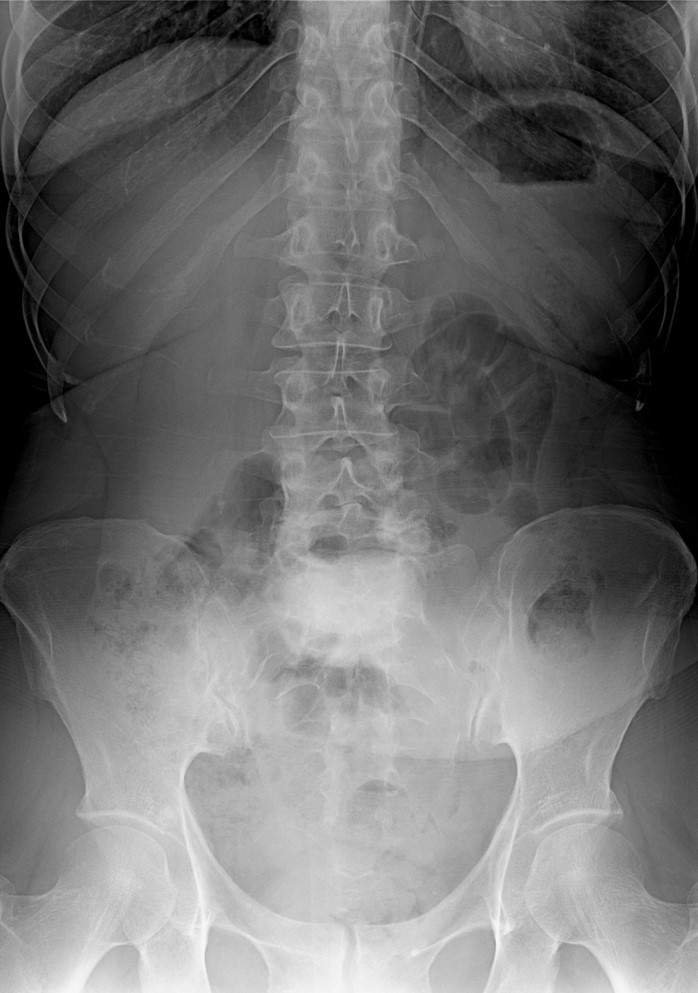

51 Yaşında Kadın Hasta

Bel ve sağ bacak ağrısı

NM normal

Ameliyat Öncesi